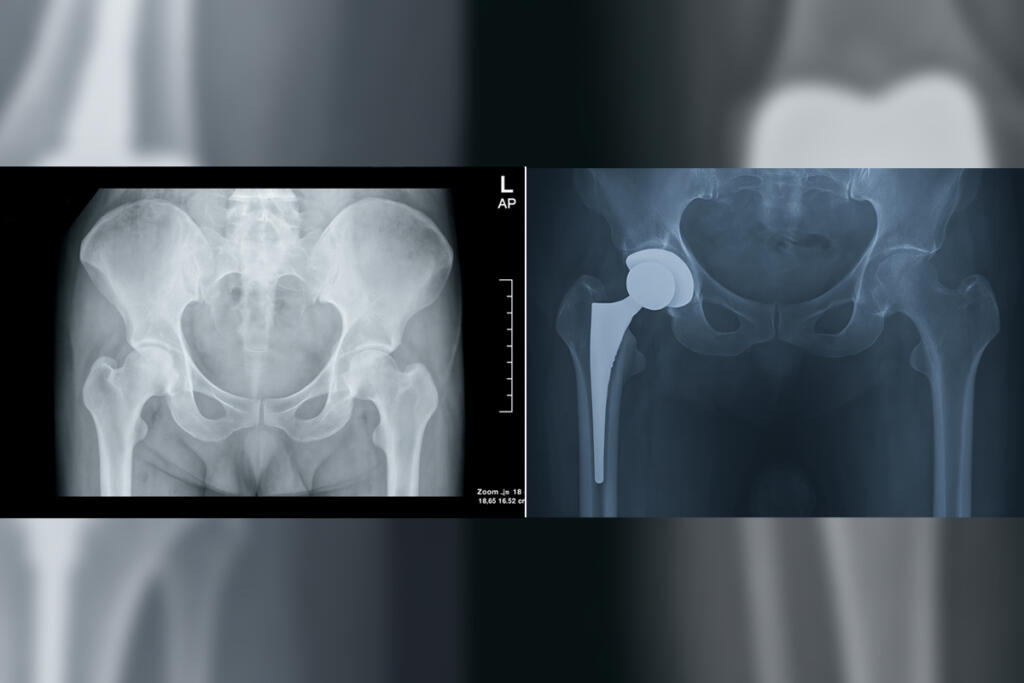

Primary Hip Replacement

Primary Hip Replacement is a surgical procedure that replaces a damaged hip joint with an artificial implant to relieve pain and improve mobility...